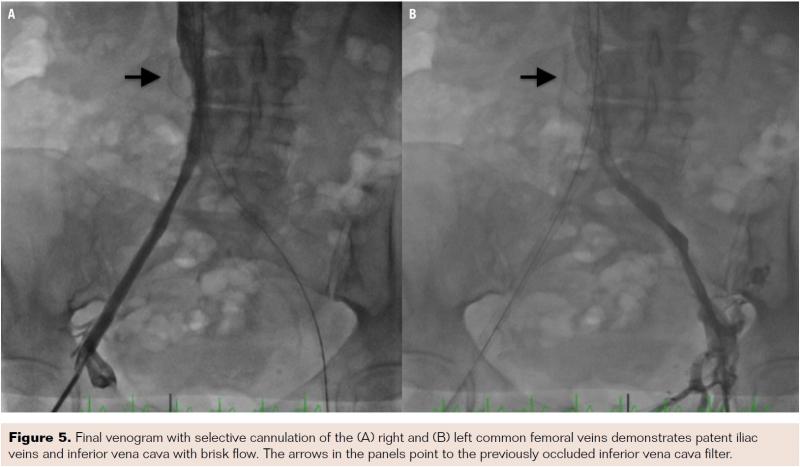

Bilateral common femoral vein access was obtained with insertion of 6 Fr sheaths. Selective right external iliac venogram demonstrated 100% occlusive disease of the distal right external iliac vein with an extensive pelvic collateral network (Figure 2). Selective left external iliac venogram showed 100% occlusive disease involving the distal left common iliac vein extending into the IVC and involving the previously placed IVC filter (Figure 3). Collaterals were noted to communicate above the level of the IVC filter. A stiff-angled glidewire with a 0.35˝ support catheter was initially used from the left common femoral vein to partially cross the occluded left common iliac vein segment; however, it failed to progress further. A Wingman catheter was then used to successfully cross the left common iliac vein into the IVC and IVC filter (Figure 4). The glidewire was then advanced above the IVC filter into the IVC, with intraluminal position confirmed by contrast injection. The Wingman catheter with glidewire was then used to successfully cross the occluded right external/common iliac vein and IVC into the IVC filter. The glidewire was again advanced above the IVC filter. Simultaneous kissing-balloon inflations were then performed in the IVC using two 6 x 150 mm balloons. Further balloon dilations were performed in each iliac vein. Intravascular ultrasound was used for accurate measurement of the IVC and iliac veins. Two 14 x 80 mm Protégé self-expanding stents (Medtronic) were simultaneously deployed in a “double-barrel” fashion in the IVC (through the IVC filter) extending into the common iliac veins. The left limb was further extended using 14 x 80 mm and 14 x 40 mm Protégé stents in the left common iliac vein. The right limb was extended with a 14 x 60 mm Protégé stent and a 12 x 60 mm Epic stent (Boston Scientific) into the right external iliac vein. All stents were postdilated with 8 mm balloons. Final venogram demonstrated patent iliac veins and inferior vena cava with brisk flow (Figure 5). The patient was discharged home the following day on aspirin, clopidogrel, and warfarin.